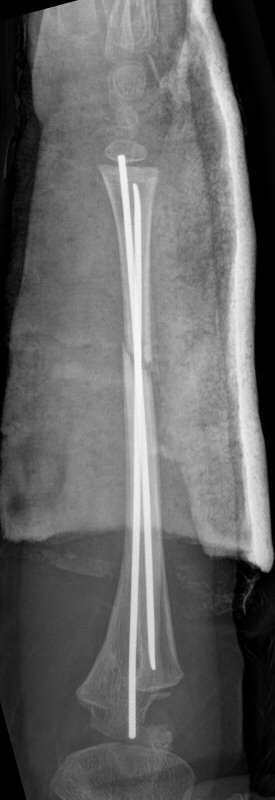

Exempel på rötngenbilder vid TEN-spikning:

Frontalbilder före och efter operation, resp. sidobilder före och efter operation med TEN-spikning i radius och ulna